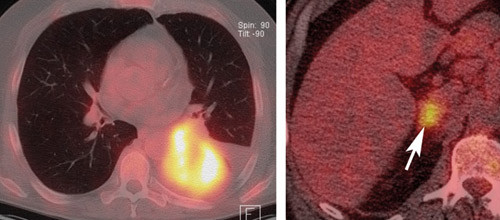

Bildet til høyre viser metastase i høyre binyre (pil) og flere steder i skjelettet (ikke vist) gjør at pasienten ikke er operabel (stadium T2bN0M1b), men i stedet er kandidat for ikke-kirurgisk onkologisk behandling.

PET/CT er egnet for stadieinndeling av lungecancer, inklusiv målrettet invasiv diagnostikk av mediastinum. Ved PET/CT kan man skille metastaser fra benigne lesjoner i binyrer og se okkulte fjernmetastaser hos 5 – 29 % av pasientene der konvensjonell stadieinndeling ikke har vist dette. Binyrer er et av de vanligste organene for fjernmetastasering fra lungecancer.